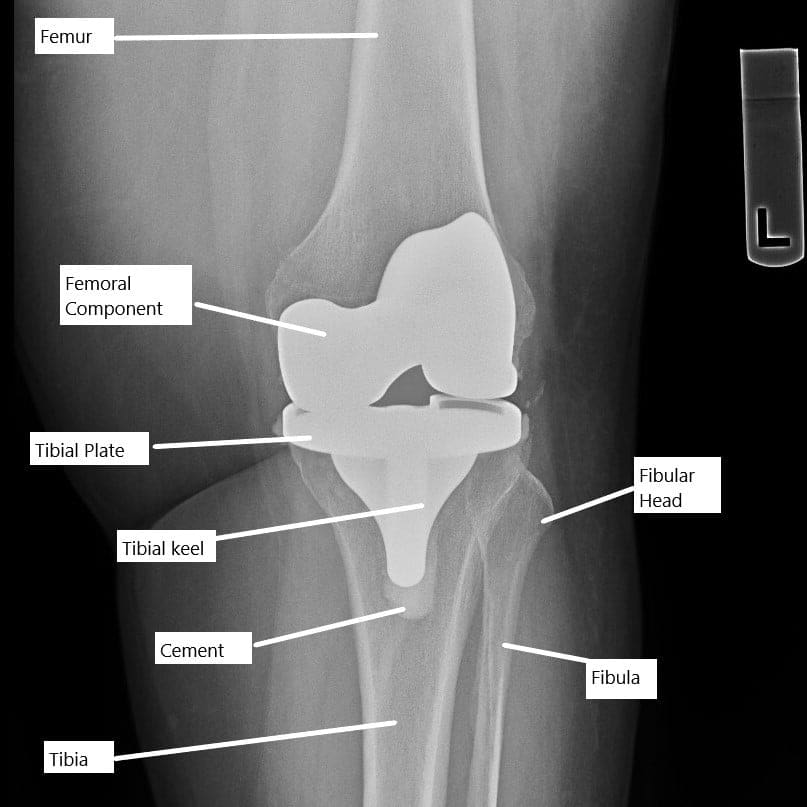

Antes de entrar en ejercicios, vamos a entender brevemente la cirugía de reemplazo de rodilla. Durante la prótesis de rodilla, las partes dañadas o enfermas de la articulación se sustituyen por componentes artificiales de metal y plástico. Este procedimiento tiene como objetivo aliviar el dolor, restaurar la función y mejorar la movilidad de personas con afecciones graves de rodilla.

Durante la cirugía, los extremos artríticos de la articulación de la rodilla se sustituyen por piezas protésicas de aleación metálica y plástico. La cirugía consiste en cortar los tejidos y el hueso para fijar las partes protésicas. Se utiliza cemento óseo para fijar las partes protésicas en los extremos del fémur, la espinilla y la parte inferior de la rótula.

La radiografía muestra un reemplazo total de rodilla.